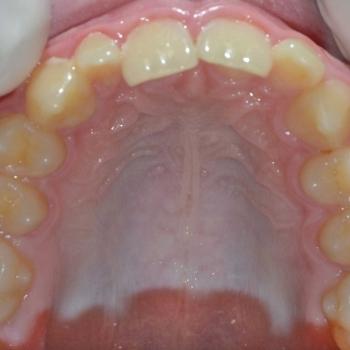

Balázs és édesanyja konzultáció céljából keresett fel, hogy egyértelműen kiderüljön számukra szükséges-e a fogszabályozó kezelés vagy sem. Már rögtön az első vizsgálat alkalmával fény derült több olyan problémára is, melyek fogszabályozást igényelnek. Ilyen volt például a súlyos mélyharapás, a hátrafelé dőlő felső metszők, illetve az Angle II. osztályú harapási eltérés is. A mintavétel, a röntgenek és a fotók kiértékelése után további problémaként merült fel a felső fogív szűkülete és a kismetszők méretaránytalansága, azaz a túlzott keskenységük.

A kezelést Quadhelix fogszabályozóval kezdtük el a felső fogív tágítása érdekében. Ezután került felragasztásra az alsó és felső fogívre a Balázs és szülei által kiválasztott fém önligírozó fogszabályozó. Ezen túlmenően Bite turbo harapásemelő segített a mélyharapás, intermaxillaris gumihúzás pedig az Angle II. osztályú harapási eltérés korrigálásában. A fogak méretaránytalansága miatt a kezelés végén a kismetszőket tömőanyaggal építettük fel, hogy a tökéletes harapáshoz résmentes fogazat társuljon. A fogak felépítéséhez az adott fogakat nem kell megfúrni, a tömőanyag kizárólag ragasztásos módszerrel rögzül, így nem károsodik a fogzománc.